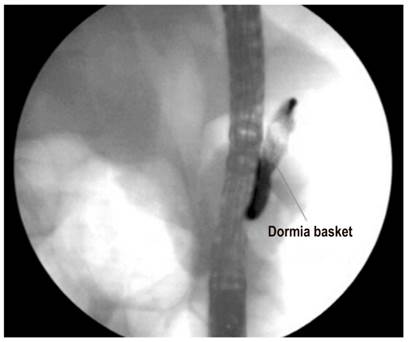

Primary pancreatic duct stones smaller than 5 mm are managed with standard ERCP maneuvers for stone removal (Figures 7, 8, 9, 10). Stones larger than 5 mm require the use electrohydraulic, extracorporeal, or Spyglass-guided electrohydraulic lithotripsy. In the latter case, the duct can be entered for use of a laser to fragment stones. 29 We have been gaining experience with the use of a cholangioscope which has been very useful for non-surgical management of patients with pancreatic stones. Figures 11, 12 and 13 show the Spyglass inside the Wirsung duct performing laser lithotripsy on a large stone. After the procedure, a pancreas stent is always placed.

Figure 9 Exploration of the Wirsung duct with Dormia basket (image courtesy of the Union of Surgeons SAS, Lázaro Arango).

Figure 10 Stone extraction from the Wirsung duct (image courtesy of the Union of Surgeons SAS, Lázaro Arango).